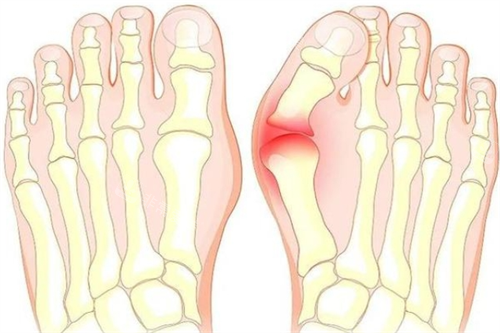

大脚骨对比图

随着病情的发展,患者的拇趾会逐渐向外倾斜,头一跖骨头内侧会出现明显的骨赘,还可能引发拇囊炎,导致红肿、疼痛。

严峻的拇外翻会影响足部的正常功能,使患者行走困难,甚至影响到膝关节、髋关节等部位的健康。